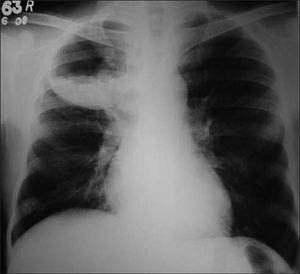

This X-Ray shows multiple air-fluid levels in the upper right lobe which is a characteristic of lung abscess.Lung abscess is suppurative inflammation of lung tissue with normal parenchyma, most commonly affects right lung. This results from autodigestion of the lung tissue by the inflammatory cells. Causes of lung abscess can be aspiration of oropharyngeal material, cancer, or bacterial pneumonia. The most common bacteria to be involved are bacteroides, peptostreptococcus, and fusobacterium. Symptoms of lung abscess include fever, malaise, cough with foul smelling sputum, weight loss and night sweats.